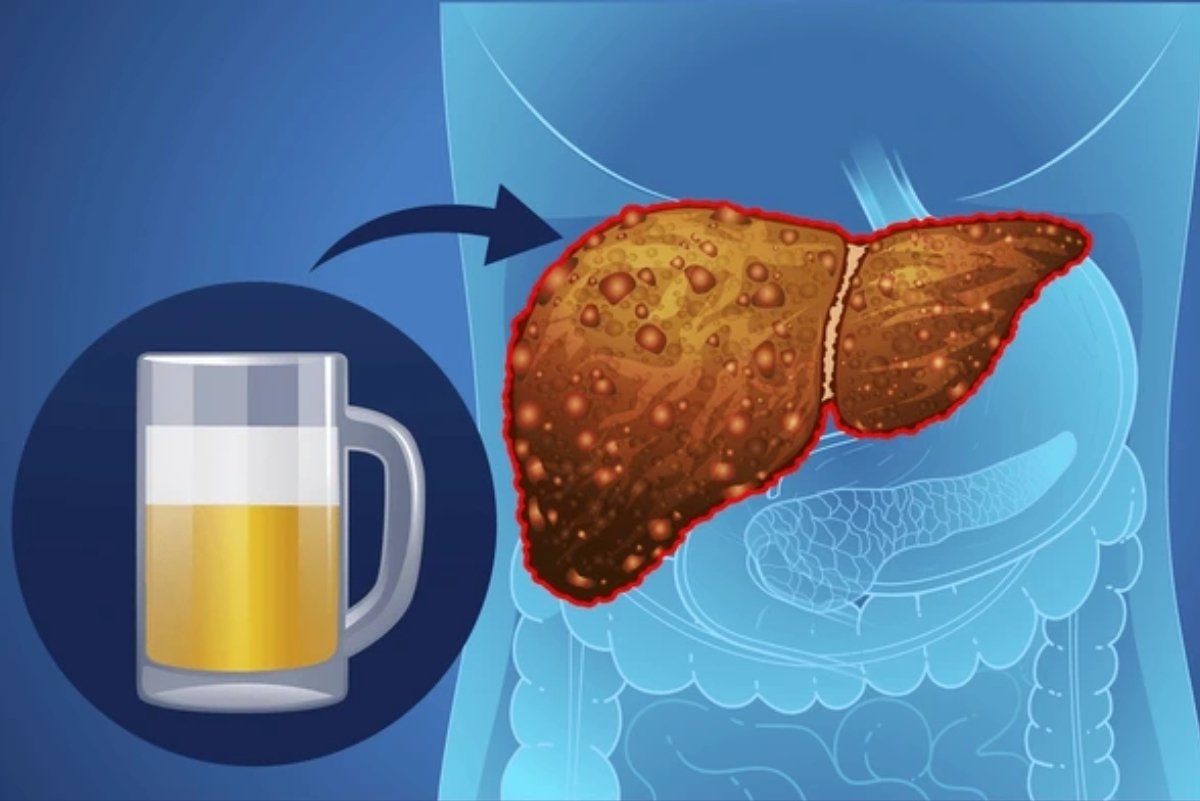

How Alcohol Consumption Affects Liver Cancer Risk